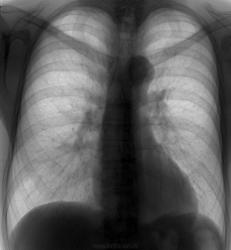

по данному рентген-снимку вполне можно предположить стеноз аортального клапана. Здесь аортальная форма сердца. Левый желудочек явно увеличен (четвертая дуга слева), если не ошибаюсь, доходит до среднеключичной линии или даже дальше. Верхняя граница дуги аорты несколько превышает тени ключиц, хотя в норме должна быть ниже их, то есть тень аорты удлинена. Это постстенотическое расширение восходящего отдела аорты - струя крови, проходя через стенозированный клапан, бьет в стенку аорты, чем вызывает ее расшиение и удлинение в этом месте.

Кроме удлинения аорты ничего не вижу ( бывает при аортальном стенозе - из-за высокоскоростного потока через стенозированный клапан), такое положение аорты в возрасте 45 лет быть не должно. А боковушка есть?

Я бы тоже порок по данным р-граммам не поставил.Если бы .как написано в выписке , был аортальный стеноз 3 ст, с кальцинозом 3+ ,то сосудистый рисунок легких дал бы о себе знать,ничего подобного на первичной р-грамме нет. Может быть клиника была ? Как то они вышли на этот диагноз?